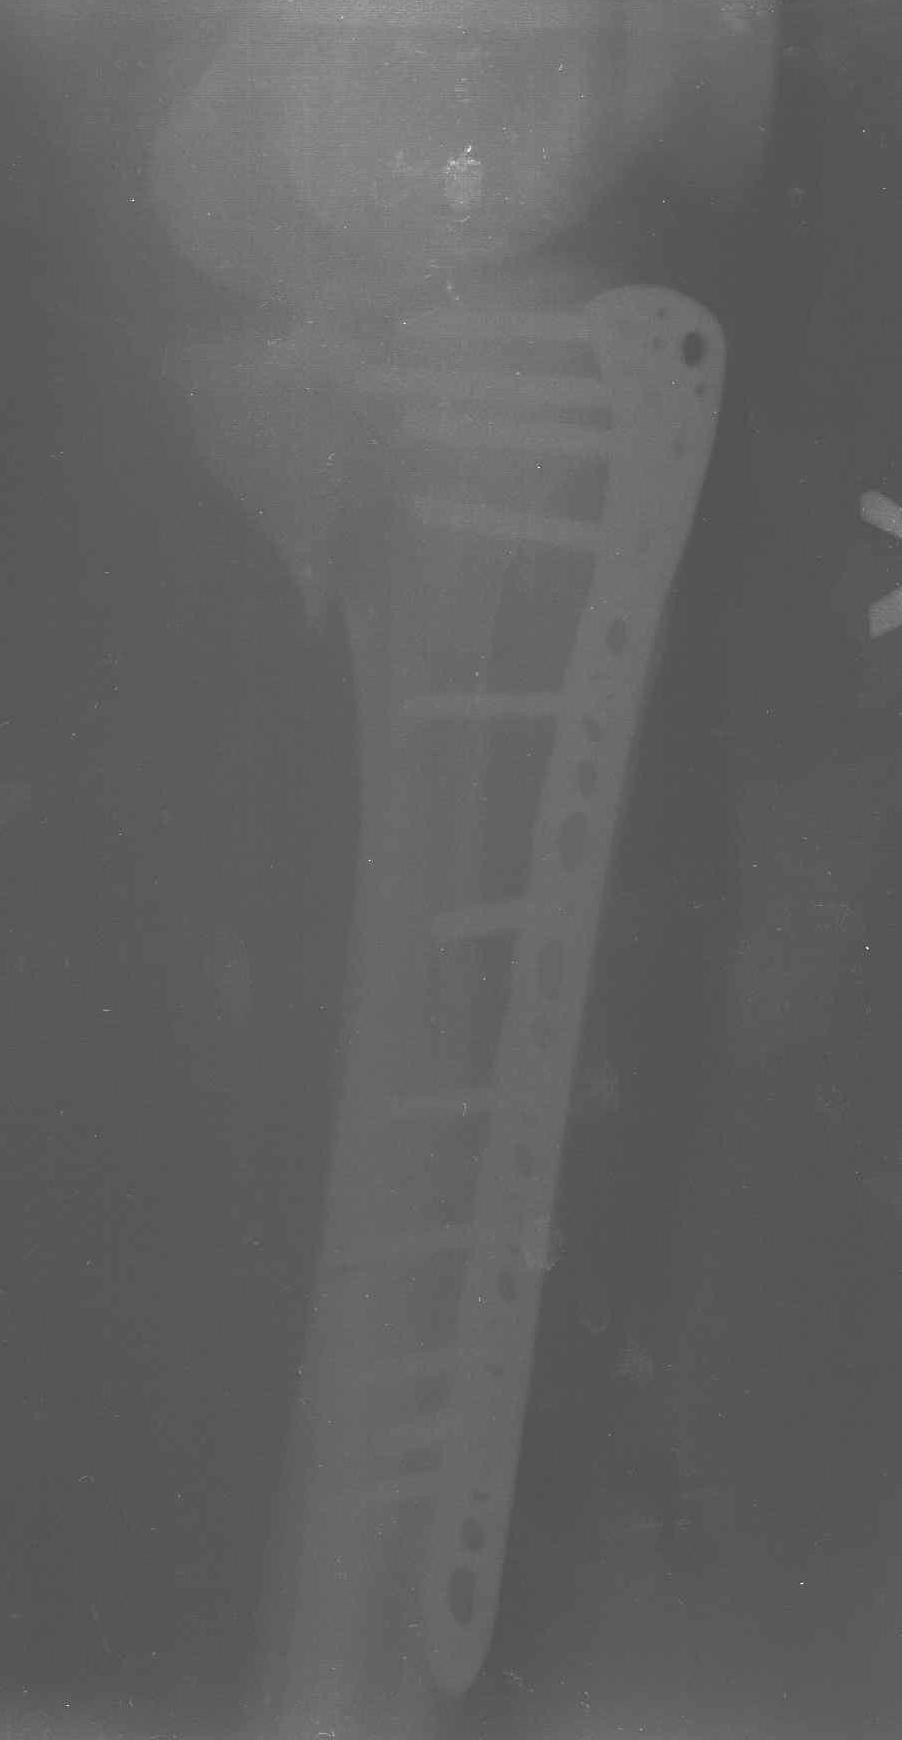

Пациенту сделали КТ - ухитрились сделать на шине Белера (не давал положить прямую ногу) - срезали передний отдел. Планируется на пятницу (24.12) на операцию - синтез длинной мыщелковой LCP-пластиной Synthes :). Отек ближе к слову умеренный (окружность голени +4 см по сравнению со здоровой). КТ и снимок на вытяжении прилагаются.

Уважаемые коллеги! В прошлую пятницу больной прооперирован - как и планировалось мыщелковая LCP от ChM. Малоинвазивно не получилось - один большой доступ :(. (но с минимальным скелетированием б/б кости). Наружный мыщелок собрали, но по контролю видно, что задне-медиальный отдел метаэпифиза смещен. Фиксировать не стали (?). 4-е сутки после операции - по м/тканям без проблем. Дополнительная иммобилизация синтетическим тутором.

P. S. перелом диафиза на контроле не совсем захвачен, но проблем там нет. Приношу извинения за низкое качество Р-грамм - выполнены на сканере (фотоаппарат не работает :)) .

Трудно поверить, что разрекламированная Ортопедическая школа Восточной Украины позволяет такие странные снимки? На прямом снимке сохранен общий контур плато, но не известна судьба импрессии суставной поверхности. На полубоковой?, оставлен без репозиции задне-медиальный отдел, и навряд ли после такой фиксации можно удовлетвориться результатом.

Такая ситуация характерна для многих, когда принимается ошибочное решение, т.е пытаются фиксировать одним имплантом переломы двух мыщелков. Латеральная пластина приемлема только для тех случаев, когда сохраняется интактным медиальный диафизарный кортекс и отсутствует фрагментация на верхушке медиального перелома.

Представленные снимки не информативны, нужны отдельные качественные снимки коленного сустава и голени без ротации.